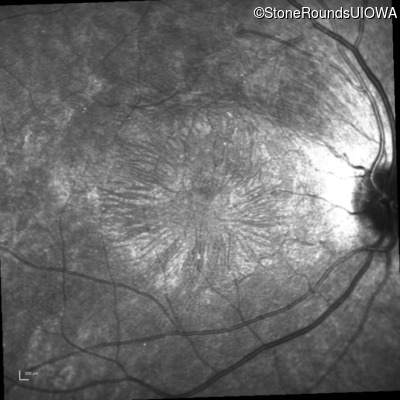

Infrared Fundus Photograph - Right -

20/20 -1

Exemplar

Infrared Fundus Photograph - Left -

20/20 -2